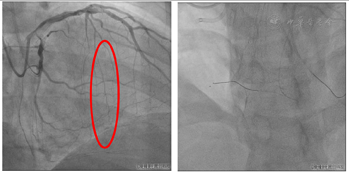

启动逆向介入治疗,逆向经1.8 F-Finecross150微导管操控SION导丝至前降支近段粗大第一间隔支各二级分支下行均不能成功进入PD(图9)。操控SION导丝经前降支中远段细小间隔支至右冠状动脉远段(图10)。但1.8 F-Finecross150微导管不能完全通过侧支循环至右冠状动脉远端,更换1.7 F-埃普特170微导管尝试仍不能通过侧支循环至右冠状动脉远端,再次更换1.8 F业聚成功通过侧支循环至右冠状动脉远端(图11)。应用反向CART技术扩张RCA中段,应用AGT技术前向送延长导管至RCA中远段,操控逆向导丝进入延长导管及指引导管,但微导管不能进入延长导管,应用拖拽技术使逆向微导管进入前向指引导管内(图12)。

前向Sion blue导丝进入逆向微导管内,回退逆向微导管至间隔支内,沿前向导丝送入SprinterLegend 2.0 mm×20.0 mm球囊扩张右冠状动脉远端(图13),因逆向微导管经过的PD血管细小,应用双腔微导管操控Fielder XT-R导丝不能至PL远端,更换Pilot 200至PL远段,退出双腔微导管,送微导管Finecross130至PL造影证实位于真腔内,更换Sion blue至PL远段,沿导丝送入Emerge 1.5 mm×20.0 mm、SprinterLegend 2.0 mm×20.0 mm球囊扩张病变(图14)。

本例间隔支侧支血管CCS分级0级,在首先选择前向导丝技术反复尝试没有成功的情况下,尝试逆向介入治疗,经近段粗大间隔支导丝无法进入右冠状动脉远端,选择考前降支中远段相对纤细的间隔支,逆向导丝可进入右冠状动脉远段,存在的问题是侧支血管细,微导管逆向通过侧支循环存在困难,连续尝试更换了3根微导管后微导管通过侧支循环到有冠状动脉远端,逆向导丝可顺利进入前向延长导管及指引导管内,逆向微导管前行困难,应用拖拽技术成功实现逆向微导管进入前向指引导管内,完成了本例PCI成功的关键环节[10]。前向导丝经过微导管対吻技术进入右冠状动脉远端,因PD细小,右冠状动脉扩张后应用双腔微导管操控导丝进入PL远段,微导管造影证实位于PL真腔内,在IVUS指导下依次球囊扩张、支架置入及应用非顺应性球囊扩张支架,取得良好的手术效果。